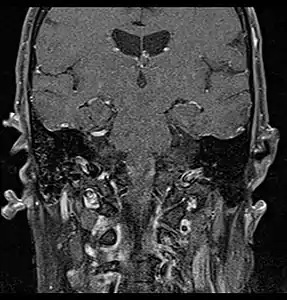

Primary treatment for this cancer, regardless of body site, is surgical removal with clean margins. This surgery can prove challenging in the head and neck region due to this tumor's tendency to show a perineural discontinuous growth, meaning that it follows nerves and different "nests" of the tumor can exist without a connection to the original tumor. Therefore, MRI-images should be analysed following nerve tracts up to the brainstem. Adjuvant or palliative radiotherapy is commonly given following surgery. For advanced major and minor salivary gland tumors that are inoperable, recurrent, or exhibit gross residual disease after surgery, fast neutron therapy is widely regarded as the most effective form of treatment.[13][14][15][16] Chemotherapy is used for metastatic disease. Chemotherapy is considered on a case-by-case basis, as data on the positive effects of chemotherapy are limited. Clinical studies are ongoing, however.

- Coronal MRI showing right parotid adenoid cystic carcinoma with perineural spread of tumor: The tumor originates in the right parotid gland and spreads along the trigeminal nerve via the auricuotemporal branch extending intracranially through the foramen ovale at the skull base towards Meckel's cave.

- Coronal MRI showing right parotid adenoid cystic carcinoma with perineural spread of tumor along the facial nerve extending to the stylomastoid foramen